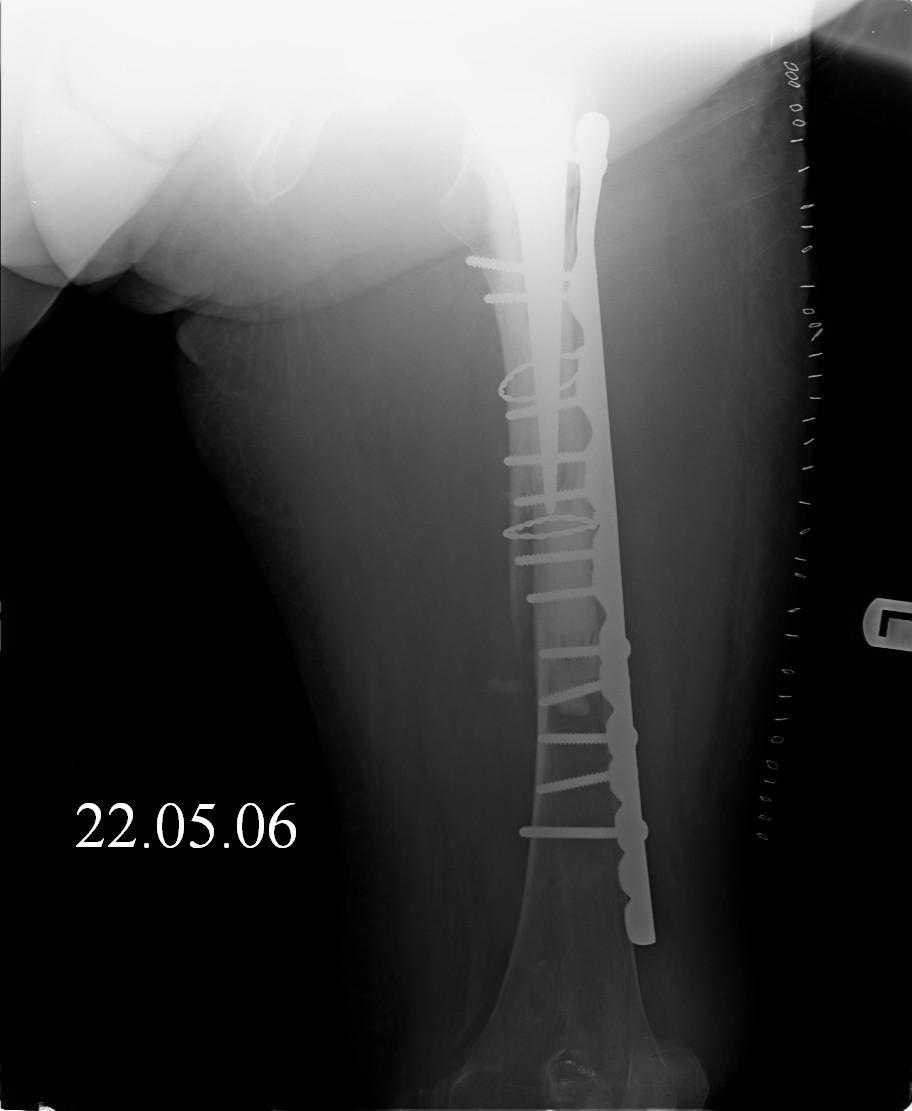

|

Reminded me of a case I did a couple years ago - 30 year old woman with juvenile rheumatoid arthritis and a nonunion below her stem. Fixed with retrograde nail which docked with the stem and a lateral locking plate. Image attached. One of the companies should come up with a stem design and nail system that anticipates this need.